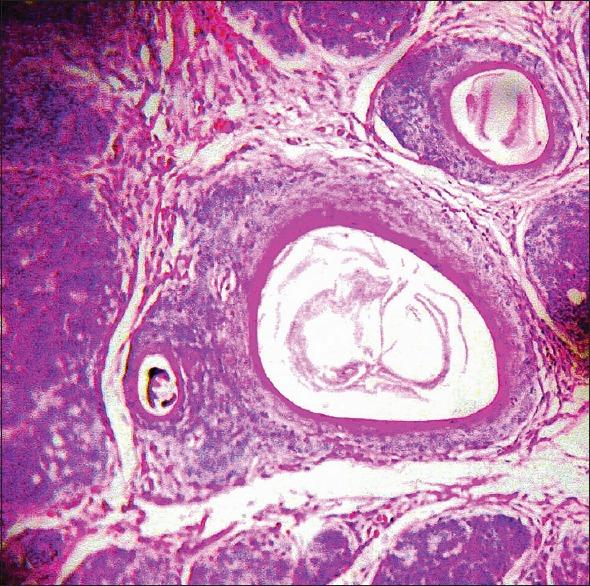

Epithelioma adenoides cysticum or multiple trichoepitheliomas are rare benign hamartomas arising from the hair germ. A 35-year-old female presented with multiple skin-colored firm papules and nodules mainly affecting the central face, scalp, and external ear canal since the age of 9 years. The lesions gradually increased with age. Her 13-year-old son also had similar but smaller lesions on the central face. Histopathology was consistent with trichoepithelioma.

囊性腺样上皮瘤或多发性毛发上皮瘤是起源于毛胚的罕见良性错构瘤。一名35岁女性自9岁起出现多个肤色坚实丘疹和结节,主要累及面部中央、头皮和外耳道。病变随年龄逐渐增多。她13岁的儿子在面部中央也有类似但较小的病变。组织病理学检查结果符合毛发上皮瘤。